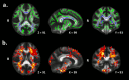

Results: Lower fractional anisotropy (FA) was observed in the pediatric-onset MS group compared to HC group within the entire WM skeleton, and particularly the corpus callosum, posterior thalamic radiation, corona radiata and sagittal stratum (all p < .01, corrected). Relative to HCs, MS patients showed higher functional connectivity involving the anterior cingulate cortex and right precuneus of the default-mode network, as well as involving the anterior cingulate cortex and left middle frontal gyrus of the frontoparietal network (all p < .005 uncorrected, k≥30 voxels). Higher functional connectivity of the right precuneus within the default-mode network was associated with lower FA of the entire WM skeleton (r = -.525, p = .02), genu of the corpus callosum (r = -.553, p = .014), and left (r = -.467, p = .044) and right (r = -.615, p = .005) sagittal stratum.